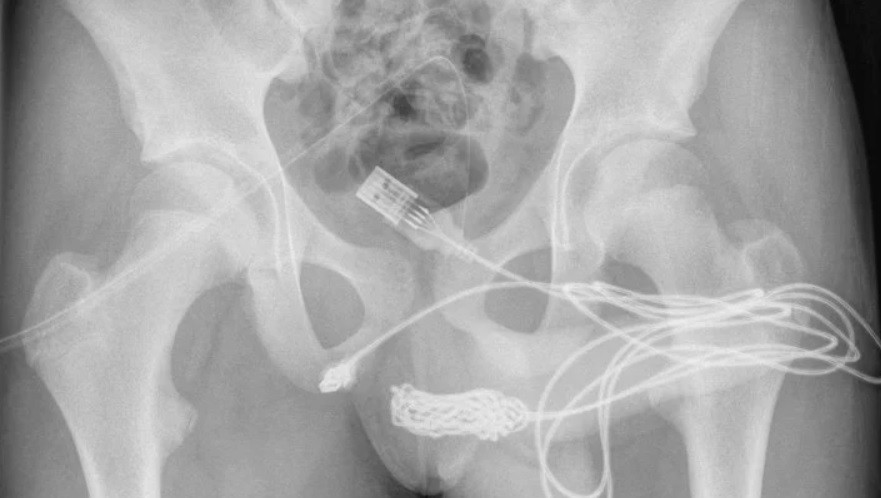

"Se descubrió que los dos puertos distales del cable USB sobresalían del meato uretral externo, mientras que la parte media del cable anudado permanecía dentro de la uretra. El paciente era un adolescente sano y en buena forma física sin antecedentes de trastornos de salud mental", indicaron los investigadores en el reporte que publicó ScienceDirect.com.

De acuerdo con esa fuente, los profesionales intentaron extraer el cable con una varilla de metal pero, debido a la gran cantidad de nudos que se habían formado, tuvieron que operar al menor.

La cirugía consistió en realizar una inserción entre los genitales y el ano del chico, para acceder a través de catéteres.

"Se realizó una incisión penoescrotal longitudinal sobre el cuerpo extraño palpable y se realizó una disección cuidadosa a través de los tejidos más profundos, dividiendo el músculo bulboesponjoso", señalaron los responsables de la intervención.

Y añadieron: "Ambos extremos del cable se sacaron con éxito a través del meato uretral externo".